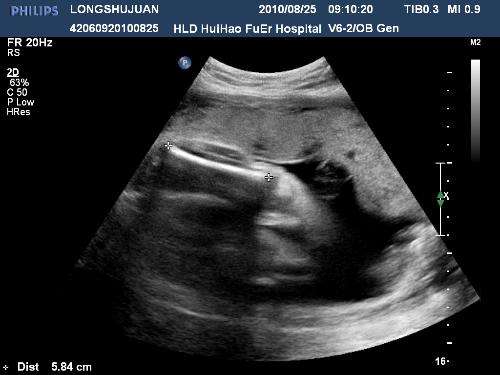

42天时去做第一次b超,就发现了有一点不对的地方,就是孕囊在左宫角那里,也许很多人,还不太了解,就是还没有到最里面,宝宝就在那里扎根了,如果乐观长长就进去了,如果不乐观,医生说就证明自己怀孕过。当然医生也不能说的那么绝对,就说明天再来一次,有专家来,再给看看。谁知这一来二去做了4次b超,让本来担心的小小,越来越担心了,心情也不再好了,这几天就哭了好几回,医生说先回家观察,只要不出血,就没有什么问题,再大一点再来观察,最主要的就是心情了。